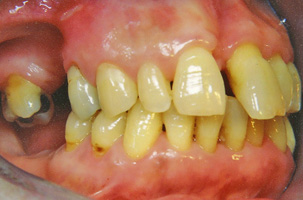

Ασθενείς που επί πολλά χρόνια δεν έχουν αντικαταστήσει χαμένα δόντια, παρουσιάζουν συχνότατα μετακίνηση των άλλων δοντιών δίπλα από τα κενά, με αποτέλεσμα να μην είναι δυνατή η πραγματοποίηση οποιασδήποτε προσθετικής εργασίας (γέφυρας, μερικής οδοντοστοιχίας, εμφυτεύματος).

Η προ-προσθετική ορθοδοντική διευθετεί τα δόντια κατάλληλα ώστε αυτά να έρθουν στις ορθές θέσεις τους, δημιουργώντας έτσι τις προϋποθέσεις για πραγματοποίηση μιας σωστής προσθετικής εργασίας.